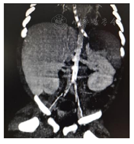

心超多次提示左心收缩功能减退,反复肺动脉高压(表1)。胸部CTA:升主动脉、胸主动脉、主动脉弓部及其分支血管壁广泛钙化;动脉导管部分未闭;冠状动脉未见异常(图1)。腹部CTA:腹主动脉及其分支(腹腔干、肠系膜上动脉、双肾动脉、双侧髂动脉及其分支)广泛血管壁钙化;腹主动脉管腔偏窄,腹主动脉分支纤细;肝、脾、胰腺、肾脏未见局灶性密度异常(图2)。基因检查(全外显子高通量测序,父母Sanger验证):ENPP1基因杂合突变,分别为来源母亲的NM_006208;exon7;c.783C>G(p.Y261X)。来源父亲的NM_006208;exon18;c.1786A>G(p.S590G),见图3。

临床症状在胎儿时期即可出现,异常钙化在胎龄18周时即有报道[3],胎儿时期可表现为羊水过多、胎儿窘迫、胎儿水肿。生后1周内起病的多数表现为心力衰竭、高血压、呼吸窘迫、发绀。后期起病的除上述表现外,也可表现为呕吐、拒奶、易激惹、生长迟缓[1]。随着年龄增长,也会出现血管外钙化,包括关节和内脏钙化。病理虽是确诊的金标准,但检查受限。实验室检查钙、磷、维生素D在正常水平[4]。有文献[5]对长期存活的患儿进行了随访,发现所有患儿在出生时血磷正常,随年纪增长平均在1岁半时出现低磷血症,2岁时出现佝偻病的比例为20%,而到13岁半时出现佝偻病的比例是100%。本案例中患儿查生化血磷在正常范围,四肢长骨片无骨质改变,与报道相符。影像学检查主要包括超声和CT。超声可帮助评估心功能,也可发现主动脉系统的广泛性管壁增厚、回声增强和管腔狭窄。CT可发现心脏瓣膜、肺动脉、主动脉及主动脉系统等大中动脉的钙化,部分病例还能发现关节周围软组织的钙化[6]。本案例为明确反复心功能衰竭和肺出血的原因进行了CTA检查,在平扫过程中即发现了广泛的主动脉系统钙化、部分管腔狭窄,提示CT平扫即可对本病有诊断作用,而增强扫描进一步排除了先天性心脏病及肺血管发育异常。基因检查多数可发现ENPP1基因异常,少数可发现ABCC6变异,其他基因变异有待进一步发掘。但需要注意的是这两个基因变异并不一定就表现为GACI,可有其他不同的疾病谱,如弹力纤维性假黄瘤、低磷血症佝偻病[7,8],故临床诊断中仍需结合病史及影像学、病理综合判断。